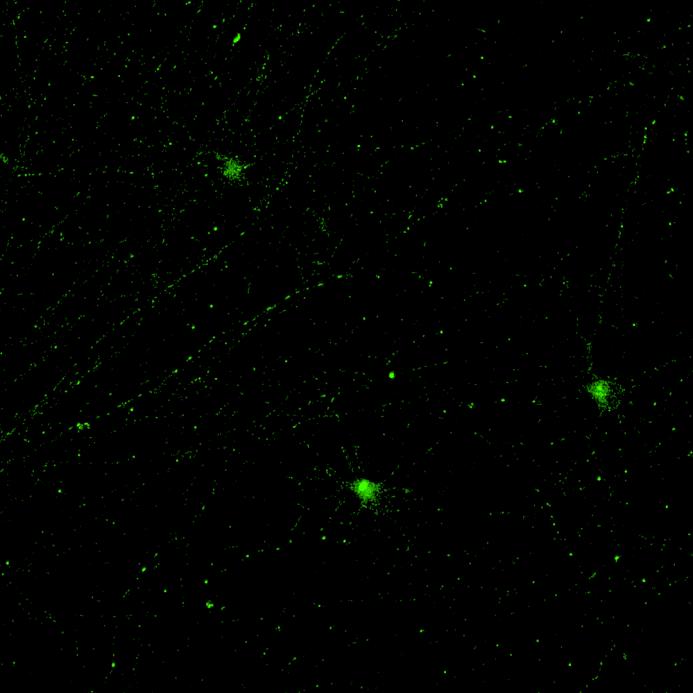

• Wildtype neurons were transduced with a lentivirus to express a full-length 4R tau isoform with a familial frontotemporal dementia P301L mutation labelled with EGFP

• Neurons were then exposed to recombinant tau preformed fibrils (PFFs) and imaged

• Increasing over time, PFF exposure induced areas of bright EGFP-positive aggregates of full-length tau, and aggregation of the K18 fragment FRET pair as seen by positive normalised FRET (NFRET) signal

0N4R-EGFP tau 2 weeks post-PFF